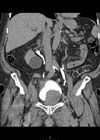

Post radical nephrectomy presenting with skull metastasis

We present the case of an 83-year-old female who underwent right radical nephrectomy for renal cell carcinoma (RCC). Despite negative surgical margins, the patient presented with a skull metastasis six years post radical nephrectomy. This case highlights the importance of...